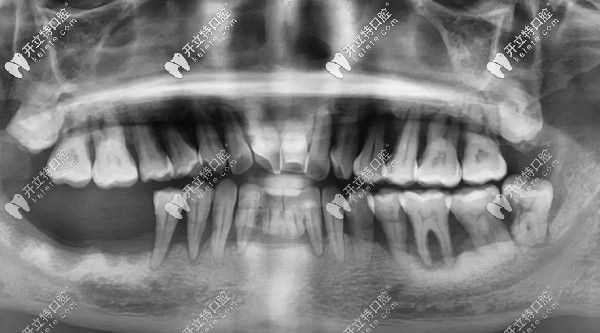

其實(shí)鄧?yán)蠋煹臐M(mǎn)口牙齒基本都在,但,一顆都留不住,因?yàn)槿慷紦u搖欲墜,牙根只有很淺一截在牙槽骨內(nèi),失去了咀嚼功能。

牙齒問(wèn)題:①牙結(jié)石沉積 ;②重度牙周炎引起牙齦萎縮,牙根暴露;③牙齒楔形缺損;④四環(huán)素牙;⑤牙齒晚上痛到影響睡覺(jué),痛的程度感覺(jué)已經(jīng)無(wú)法忍受了;⑥輕輕咬一點(diǎn)東西牙齒都在里面動(dòng)....

鄧?yán)蠋煹闹髟\醫(yī)生王鋒表示:“楔形缺損和四環(huán)素牙會(huì)使牙齒對(duì)外界刺激變得敏感,但讓全口牙齒松動(dòng),一吃東西就痛的“元兇”,其實(shí)是長(zhǎng)年得不到治療的牙周病?!?/p>